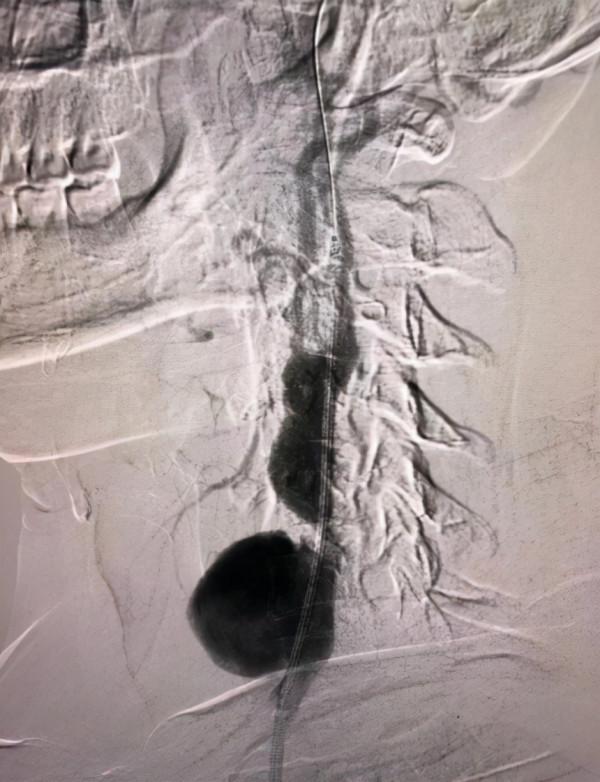

劉建林主任評估患者病情及檢查結果後,考慮頸動脈假性動脈瘤修復手術需全麻插管。術中造影顯示,左側頸總動脈中段血管破裂,區域性假性動脈瘤形成,瘤體較前明顯增大,破裂風險增加,在王吉昌主治醫師、劉嘉欣住院醫師協助下為該患者實施了介入微創手術,經準確測量及造影定位,放置一枚支架於破口位置,即在大腿根部行血管穿刺,將帶覆膜的支架植入到頸動脈破口處,從而阻隔頸動脈的破口,通俗的說是給血管加了個不滲血的“內襯”。手術過程順利,患者左頸部包塊搏動消失,目前病情穩定。術後超聲檢查提示瘤體內血流訊號顯示,提示破口被完全封閉。

術中造影結果,提示左側頸總動脈中段血管破裂,區域性假性動脈瘤形成